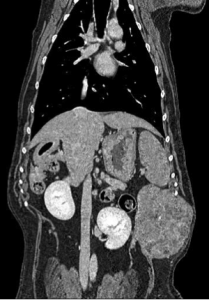

今回は左最後肋骨の中央に発生しており、かつ体壁の内側に成長していたために発見が遅れたと推測されます。サイズはφ10cm大で皮膚への固着はありませんでした。CTでは、肺野の転移像はなく脊椎への浸潤も確認されませんでした。

CTより肋骨から派生した腫瘍が疑われました。CTでも明らかな肺転移は確認されませんでした。